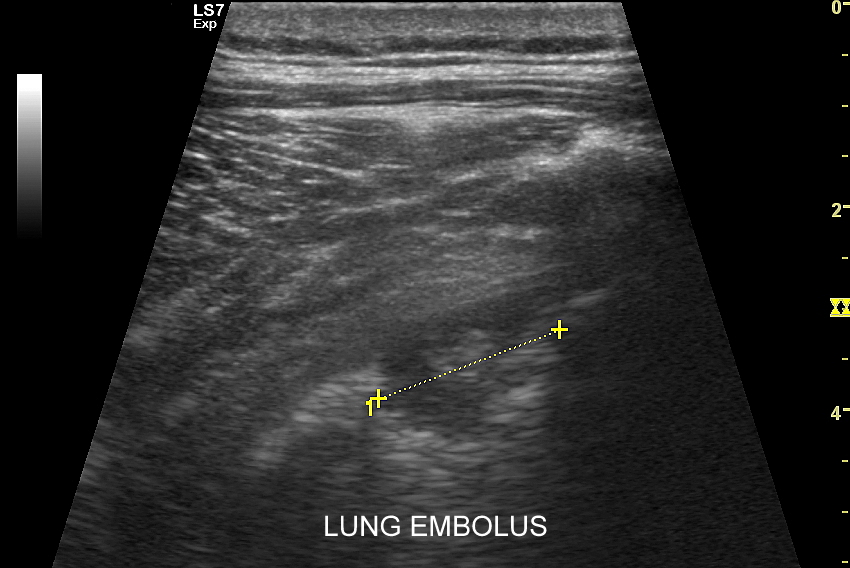

Kluczem do wartościowego zastosowania metody USG w diagnostyce pulmonologicznej jest zrozumienie jej możliwości oraz ograniczeń. USG jest niezwykle czułym badaniem w diagnostyce zapaleń płuc zarówno płatowych, jak i atypowych, np. wywołanych przez Mycoplasma lub Chlamydia. W przypadku zapalenia płuc pojawienie się widocznych zmian sonograficznych wyprzedza wystąpienie fenomenów osłuchowych wykrywanych przy osłuchiwaniu klasycznym stetoskopem. Metoda USG jest również bardzo czuła w diagnostyce chorób opłucnej i jam opłucnowych, takich jak nowotwory opłucnej, odma odma opłucnowa czy płyn w jamie opłucnowej. W rękach doświadczonego lekarza badanie USG może być przydatne w wykryciu zatorowości płucnej, a nawet guzów nowotworowych płuc.

USG płuc | Można powiedzieć, że Pan Doktor uratował życie mojego Taty. Wykrył w USG zakrzep w płucu, którego nikt wcześniej nie zauważył. Gdyby nie to mój Tata mógłby się udusić w trakcie ataku. Dziękujemy serdecznie. Dominika K. | Polska

USG płuc | Od tygodnia utrzymywał się u mnie kaszel i ogólne rozbicie, następnie dołączył się ból w okolicy nerki, u podstawy szyi i w klatce piersiowej. Można było pomyśleć, że to przeziębienie oraz kolejna kolka nerkowa. Na szczęście podjąłem decyzję, aby udać się do przychodni, gdzie przyjmował znany mi dr Szczepański. Doktor mnie wysłuchał, osłuchał i wykonał USG. Rozpoznanie zator płucny i skierowanie do szpitala. Zator potwierdzony w tomografii komputerowej i szybko rozpoczęte leczenie. Dlatego żyję! Tomasz S. | Wrocław